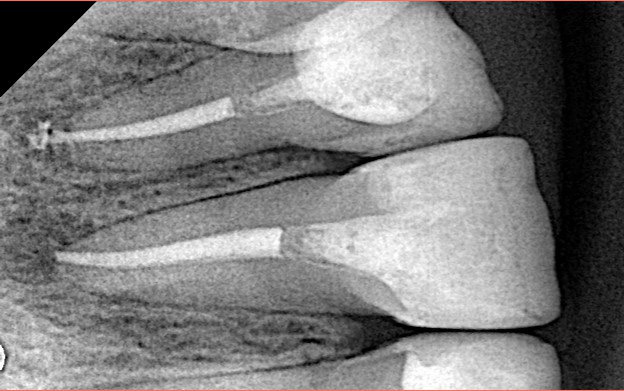

Endodontic Re-treatment for upper central incisor, Endodontic treatment for upper lateral incisor.

Bioceramic sealer and single cone for obturation.